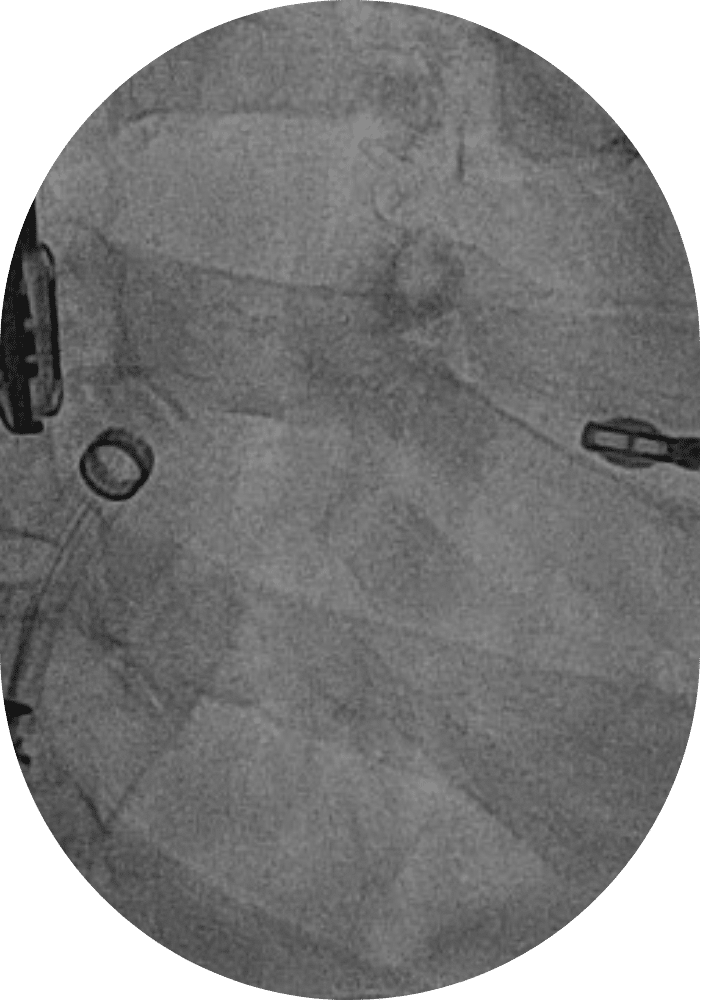

Fermeture Foramen Ovale Perméable (FOP)

Avant la naissance, les deux chambres supérieures du cœur (les oreillettes) communiquent, laissant passer le sang de l’une à l’autre. Ce passage (Foramen Ovale) doit se boucher au cours de la première année de vie, on parlera de Foramen Ovale Perméable s’il persiste au-delà. Le FOP est présent chez de nombreuses personnes et ne pose généralement pas de problème. Toutefois, il peut être à l’origine d’AVC ou d’embols d’autres artères. Une intervention peut donc s’avérer nécessaire.

Une sonde supportant le système de fermeture est insérée dans la veine fémorale (dans l’aine) et guidée jusqu’au cœur. Une prothèse en forme de parapluie est alors déployée pour sceller l’ouverture du FOP.

Cette intervention très peu invasive et rapide (moins d’une heure) est réalisée sous anesthésie générale. Les patients peuvent généralement sortir dès le lendemain.

Fermeture Foramen Ovale Perméable